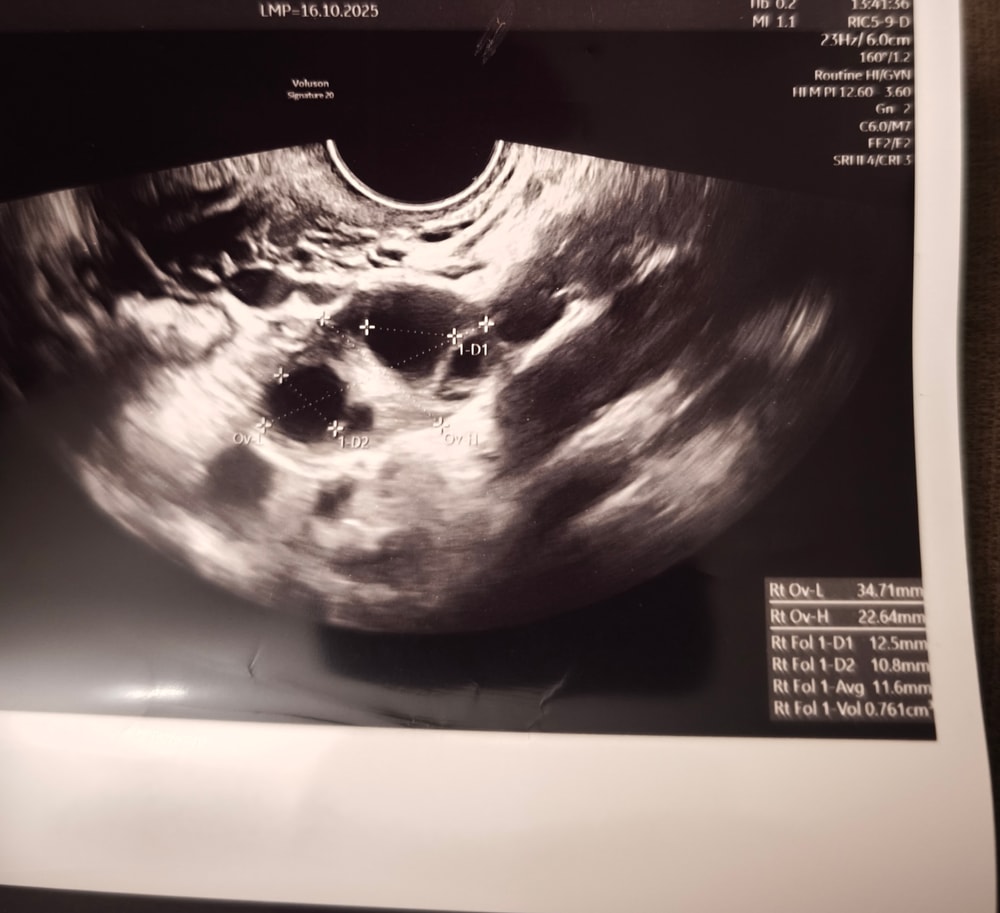

Какой размер фолликула

Лена, один 12,5, другой 10,8. Третий размер это похоже среднее (Avg=average)

Калина красная, ну вот он меня и смутил Это наверно мало для 13 ДЦ?

Лена, норм, просто О может быть чуть позже

Фолликул на 13 дц Фоликул